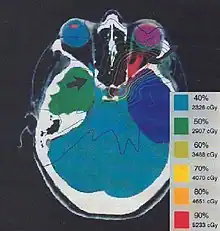

The more formal optimization process is typically referred to as forward planning and inverse planning.[12][13] Plans are often assessed with the aid of dose-volume histograms, allowing the clinician to evaluate the uniformity of the dose to the diseased tissue (tumor) and sparing of healthy structures.